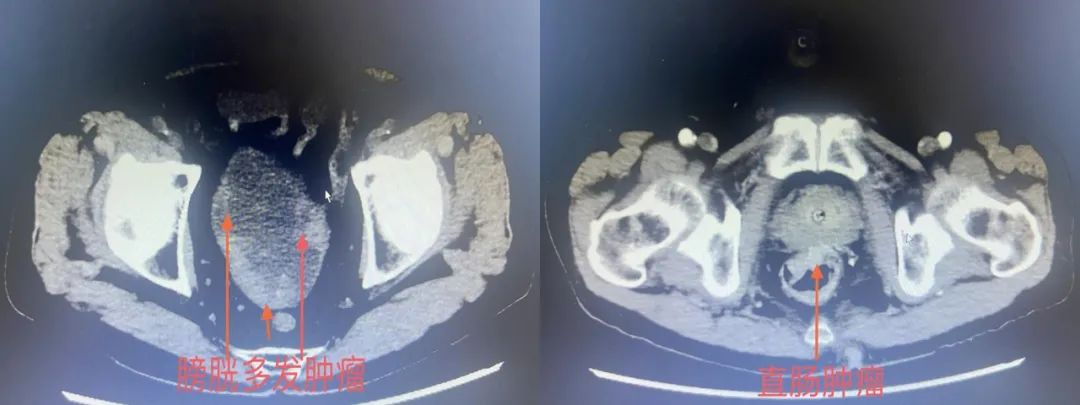

▲患者术前CT结果

患者入院后进行CT检查后发现膀胱恶性肿瘤。但CT检查同时也发现直肠下段和乙状结肠占位性病变,考虑恶性肿瘤。泌尿外科为何大爷进行了膀胱镜以及肠镜检查,结果显示何大爷同时患上了膀胱恶性肿瘤和结直肠恶性肿瘤。而各项检查都提示何大爷患有重度贫血、重度肺功能不全。摆在眼前的问题非常严重,一般人患上膀胱癌已经是难以承受的了,但何大爷同时患上结直肠恶性肿瘤。何大爷不仅80多岁高龄,身体情况还非常差。对于这种情况,大多数医生都会建议患者保守治疗,不要再考虑手术了。